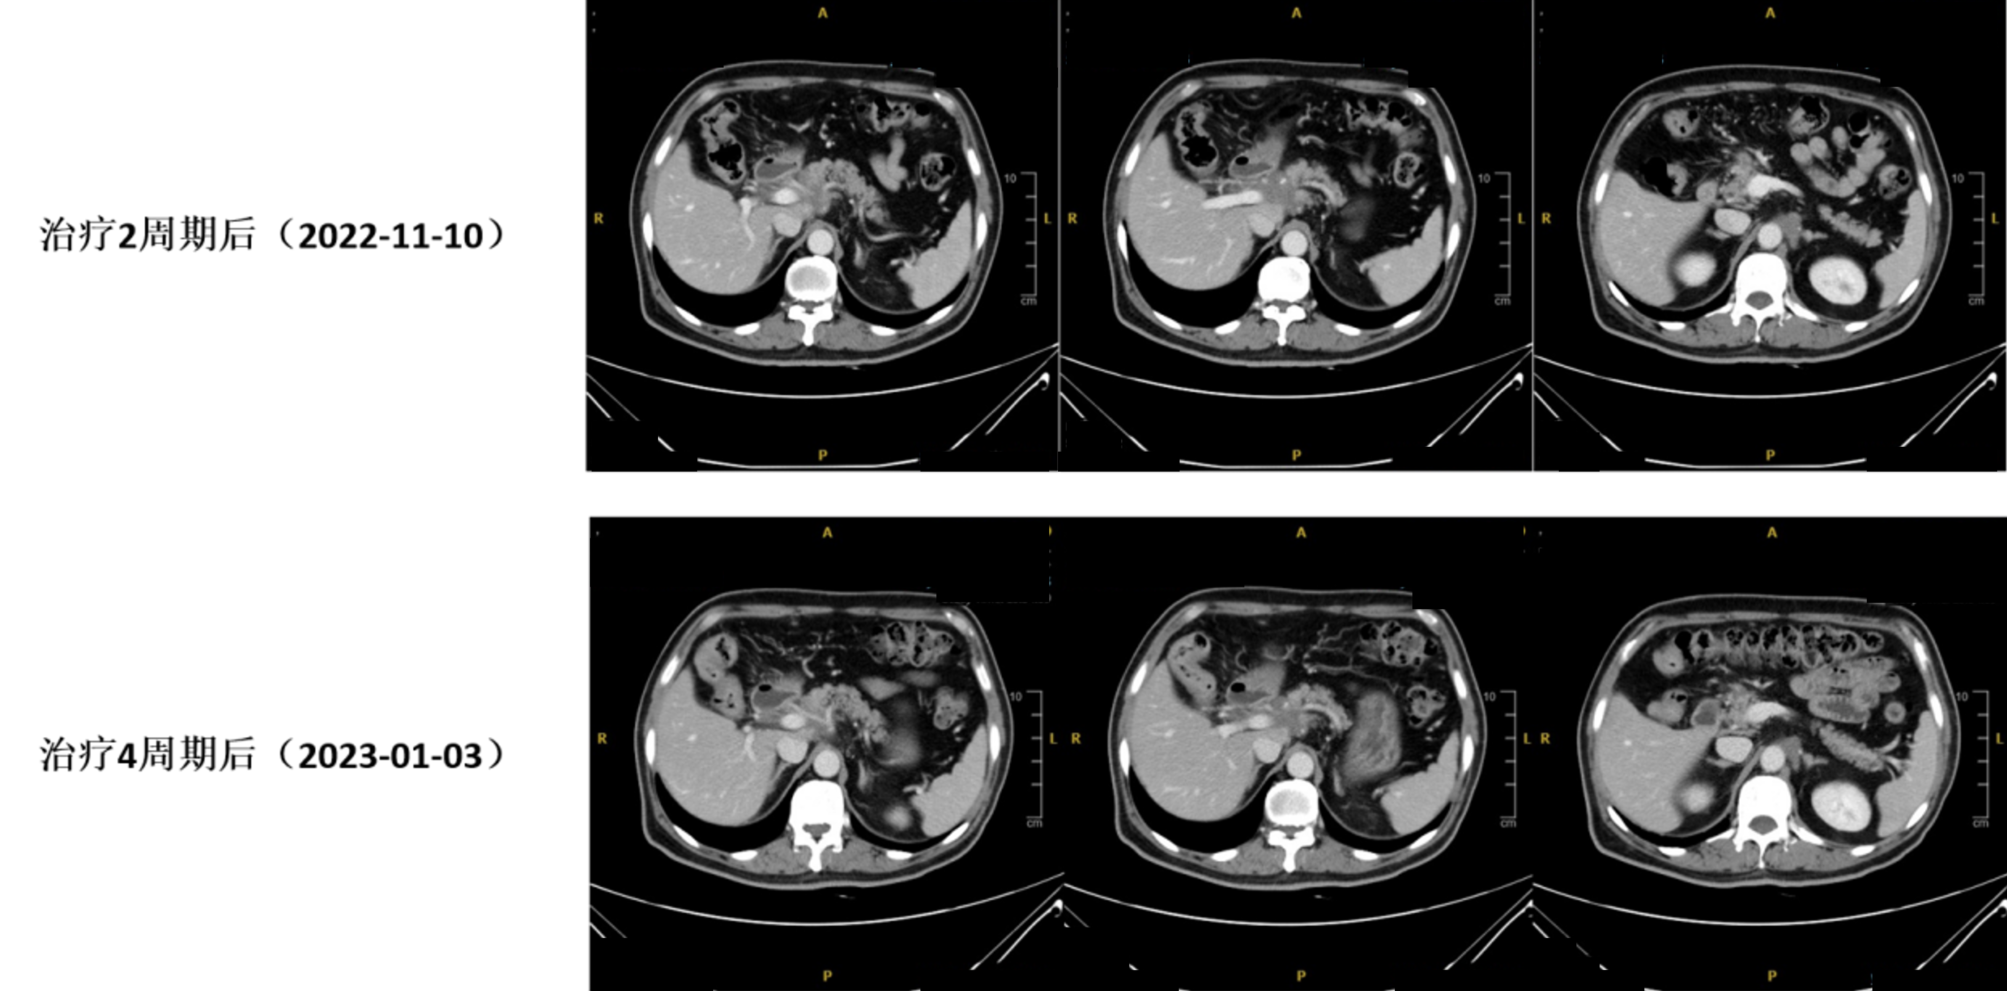

2周期治疗后疗效评估(CT复查:2022年11月10日): 胃窦病灶较前好转。胰腺颈部病灶较前退缩,肝门区、肠系膜根部、腹腔动脉根部、腹膜后多发转移淋巴结较前缩小。

1752039198171.jpg

图2. 治疗前(2022年09月21日)与治疗2周期后(2022年11月10日)CT对比

4周期治疗后疗效评估(CT复查:2023年01月03日): 胃窦胃壁稍增厚,较前变化不大;胰腺颈部病灶较前稍退缩;腹腔、腹膜后多发肿大淋巴结较前稍缩小。

6.jpg

图3. 治疗2周期后(2022年11月10日)与治疗4周期后(2023年01月03日)CT对比